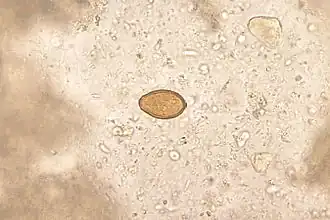

Il vit sur, et parfois dans la muqueuse du tiers moyen du grêle. Il pond de petits œufs (30 microns) ovoïdes, operculés, transparents, qui sont éliminés avec les selles. Le cycle comprend deux hôtes intermédiaires, un gastéropode d'eau saumâtre (Pirenella conica), qui avale les œufs, et un poisson d'estuaire (mulet, tilapia) dans les muscles duquel s'enkystent les métacercaires infectieuses. C'est en mangeant ces poissons mal cuits que l'homme s'infecte.

Le diagnostic de certitude sera obtenu par la découverte, dans les selles, des œufs caractéristiques.